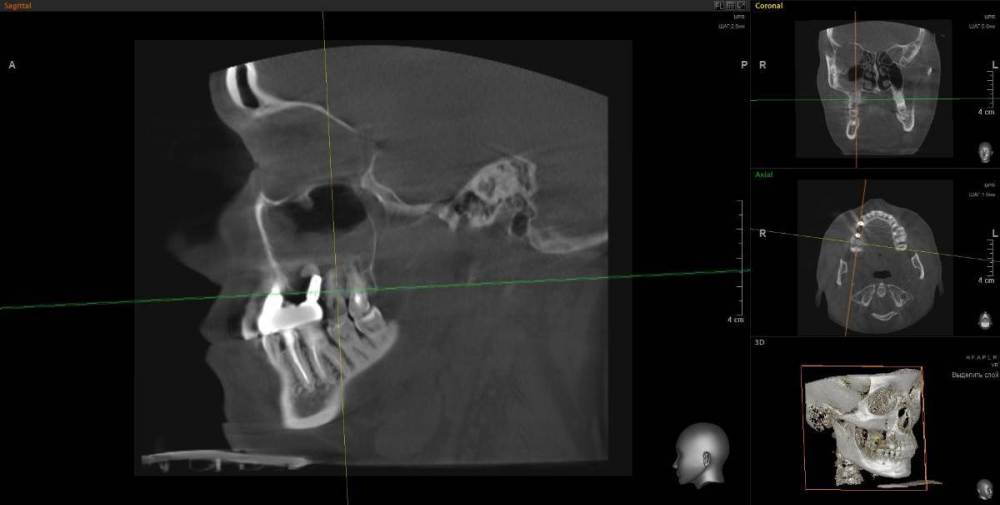

1. Из-за сильного воспаления верхнего зуба костная кость растворилась и дошло до пазух носа. Зуб рекомендуют удалить

2. Импланты установила 2 года назад, в итоге заплачено было 200 тыс. с учетом циркониевых коронок. На КТ обнаружилось сильное воспаление, как следствие растворилась костная ткань импланты, доктор сказал уже не спасти.

IMHO. Зуб 18 стоит удалить, зуб 17 стоит полечить. Имплантат в позиции 16, похоже, придётся удалить, имплантат в позиции 14, на мой взгляд, вне опасности.